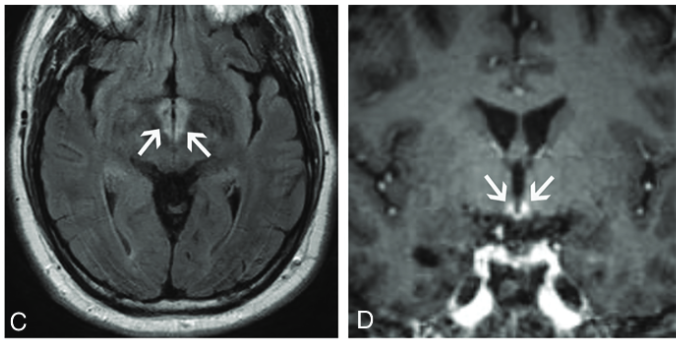

脳:辺縁系脳炎

画像所見

典型的な画像所見は内側側頭葉のT2高信号と腫脹である.時に,造影効果を伴う.FDG-PETでは代謝亢進を認めうる.

他の辺縁系の部位にもこれらの所見が生じることがある(視床下部や乳頭体に明瞭な病変を認め,他の辺縁系は保たれることがある).海馬や扁桃体などの典型的な部分が障害されていない場合でも考慮する必要がある.

時に辺縁系脳炎は占拠性病変に似た画像を呈し,low grade~high gradeグリオーマやリンパ腫と誤認されうる.